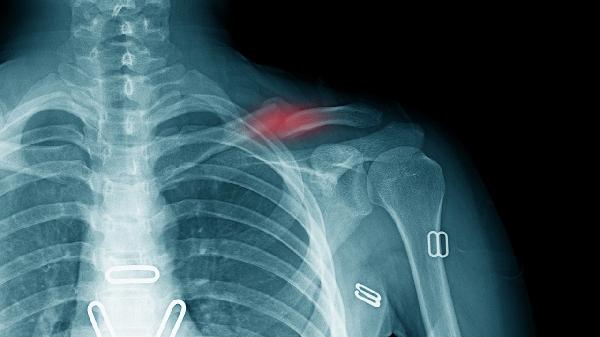

X线或CT显示骨折线持续存在、骨痂形成不足、内固定松动或断裂。影像学是确诊骨不连的金标准,可明确骨缺损范围和愈合阶段。根据结果选择保守观察、体外冲击波或再次手术治疗。